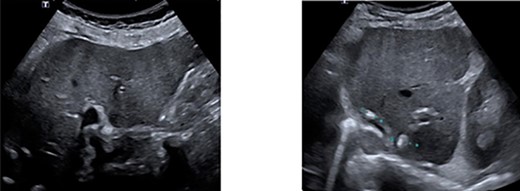

As part of follow-up 6 months after resection, laboratory tests for CEA, an ultrasound of the liver and a colonoscopy were performed. Postoperative CEA was 4.0 ng/mL. Ultrasound of the liver showed post-therapeutic changes after RFA and surgery. No metastases were found (Fig. 3). With colonoscopy, one polyp was found in the caecum. A punch biopsy was performed and revealed an adenoma with low-grade dysplasia.

Ultrasonography of the liver showing no progression of disease. A. Right lobe. B. Left lobe.